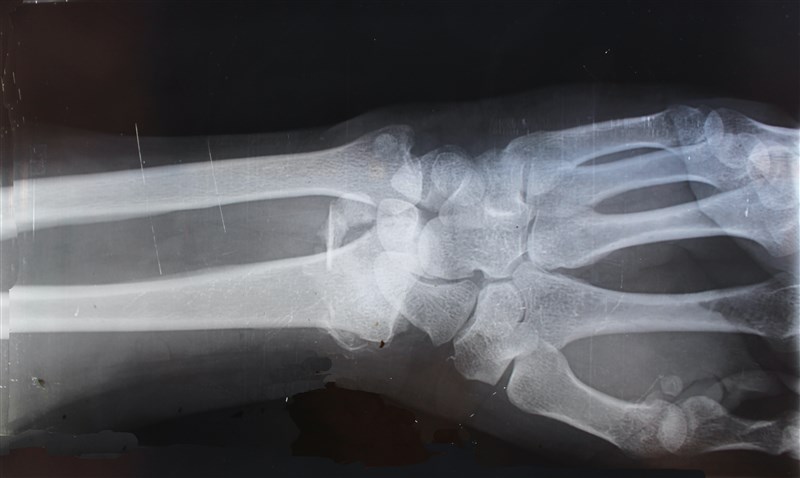

糖尿病導致骨質疏鬆 吃鈣質維生素D防骨折 |2020.11.09 語音朗讀 3239觀看次 字級 大 中 小 圖說:糖尿病和骨質疏鬆相關,糖尿病患應提早重視骨質疏鬆和骨折風險,應均衡飲食,積極控制血糖,適量運動增加肌肉協調性、補充維生素D、鈣。圖/Unsplash 【本報台北訊】國內外有愈來愈多研究顯示,糖尿病患比沒有糖尿病的同齡者發生骨質疏鬆機率高,且發生髖部骨折者也比同齡非糖尿病患高2倍以上。林口長庚醫院新陳代謝科醫師黃兆山表示,糖尿病的高血糖會引起骨頭脆弱,不僅會造成皮質骨縫隙變大,還會影響骨頭結構和品質變化,糖尿病患應提早預防骨質疏鬆,降低骨折風險。糖尿病有較高的骨質疏鬆、骨折風險,黃兆山解釋,主因是糖尿病患的類胰島素生長因子(IGF)異常以及糖基化產物(AGE),影響膠原蛋白組成及骨細胞代謝異常,讓骨頭結構和品質發生不良變化,提高骨質疏鬆風險。此外,糖尿病併發腎病變時,會影響維生素D的活化與合成,造成鈣離子流失,胰島素增敏劑(TZD)藥物也會抑制造骨細胞生成,使骨質密度下降,因此糖尿病患有較高的骨質疏鬆和骨折風險。圖/Unsplash根據世界衛生組織對於骨質密度,定義骨質疏鬆症的分級方式,T值大於-1代表正常;介於-1至-2.5之間則是骨質不足 ;小於-2.5代表骨質疏鬆症。許多糖尿病患往往會低估骨質疏鬆,尤其是第二型的糖尿病患,黃兆山提及,「骨密度測量往往反應不出來,骨密度看似正常或偏高(T值>-2.5),卻有高骨折風險」,因此錯過最佳預防時機;第一型的糖尿病患好發於年幼階段,巔峰骨質(骨骼達到最大強度和密度)會較低,提高未來骨質疏鬆的風險。黃兆山分享,一名55歲在浴室滑倒造成腰椎骨折的糖尿病患,送醫檢測骨密度值為-2.2,評估雖未達骨質疏鬆卻造成骨折,「糖尿病患者常常誤以為,骨密度未達-2.5就不是骨質疏鬆,對糖友來說,即使骨密度未達-2.5也應非常留意,提早治療才能遠離骨鬆危機。」圖/Pixabay除了骨骼代謝異常,糖尿病還會造成周邊神經病變、視網膜病變、神經功能障礙等,易因視力不清楚增加跌倒機率,黃兆山強調,糖尿病藥物如「胰島素增敏劑(TZD)」、「排糖藥物」抑制造骨細胞,會造成骨質密度下降。如果同時患有骨質疏鬆和糖尿病患者,黃兆山提醒,用藥需格外小心,盡量避免惡化骨質的藥物,同時補充足夠的鈣質和維生素D,積極治療穩定骨質。圖/Pexels糖尿病與骨質疏鬆兩者關係非常密切,骨骼變化引發的骨折風險相當大,有些骨折患者引發急性疼痛、長期臥床,或需長時間復健、行動受限,長期影響病患的生活品質,增加死亡率。黃兆山呼籲,糖友們應提早重視骨質疏鬆和骨折風險,若診斷骨質疏鬆症,應均衡飲食,積極控制血糖,延緩糖尿病併發症,適量運動增加肌肉協調性;若有高骨折風險的病患,應補充維生素D、鈣,及骨質疏鬆藥物治療,避免服用會惡化骨質的藥物,提早預防和積極治療,全面遠離併發症和骨鬆危機。健康醫療網:https://www.healthnews.com.tw/blog/article/47923/ 前一篇文章 擦撞路邊車沒人看到快閃? 警方:離開就觸法 下一篇文章 新冠病毒》全球確診破5000萬 歐洲3天增100萬成重災區 熱門新聞 01法華禪寺深化宗教交流 拜會斯里蘭卡駐法大使2026.01.1602告急! 全台血庫剩5.3天 O型最缺2026.01.1603全球共讀《傳燈錄》 人間佛教雲端點燈2026.01.1604【生活快門】環保地球儀2026.01.1605【時光重逢】心裡有荷‧李蕭錕書畫照見初心2026.01.1606安心過年 海天佛剎送暖福田戶2026.01.1607大腦發炎易引發焦慮 吃莓果橄欖油助修復2026.01.1608舞獅躍動 馬德里佛青展現所學2026.01.1609【翻轉人生】修好機車 修好人生2026.01.1610【女子生活學】月亮忘記了2026.01.16 訂閱電子報 台北市 天氣預報 台灣一週天氣預報 相關報導 海鯤號再現身 海測前做準備汽車與農產品 美要求開放市場台美關稅談判 鄭麗君今說明周折汪喵嘉年華 總統籲零棄養高雄新材料循環產業園區台半導體供應鏈 4成移美